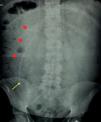

La forma de aparición de los pseudoquistes es generalmente mediante clínica abdominal muy inespecífica. La etiología más validada es la existencia de una infección concomitante del sistema de derivación del LCR, y como tal el tratamiento precisa antibioterapia y sustitución de todo o parte del sistema. Sin embargo, el pseudoquiste no necesita de un tratamiento activo, salvo casos concretos. Este manejo, presentado algorítmicamente en el presente trabajo, logra una tasa de recurrencia menor que otras opciones que, no obstante, sigue siendo importante, y se asocia además a otras complicaciones de las derivaciones relacionadas con varios factores.

The clinical presentation of pseudocysts is normally through non-specific abdominal symptoms. The most validated etiology consists on the existence of a concomitant infection of the CSF shunt system, and so, treatment needs of antibiotherapy and total or partial substitution of the system. However, the pseudocyst itself doesn’t need an active treatment, except for some specific cases. This management, algorithmically presented in the present work, achieves a lower recurrence rate than other options, but this one is still important, and is also associated with other complications of those shunts related with several other factors which need to be taken in account.